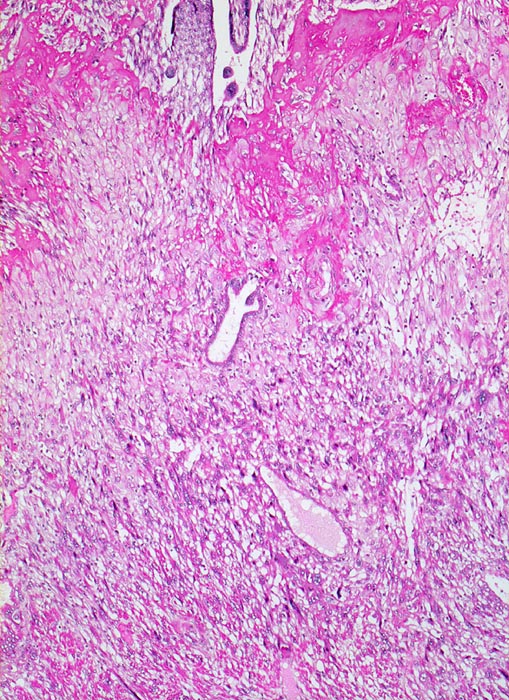

Oben im Bild Anschnitte des proliferierten Trophoblast der Haftzotten. Daran angrenzend eine homogene rote Schicht von Fibrinoid und darunter die Infiltrationszone des intermediären extravillösen Trophoblast im Bereich der Dezidua. Die hellen blasigen Zellen entsprechen der Dezidua. Diese wird infiltriert von intermediären Trophoblastzellen mit dunklem Zytoplasma und grossen hyperchromatischen Kernen.

11. Schwangerschaftswoche. Normale Schwangerschaft